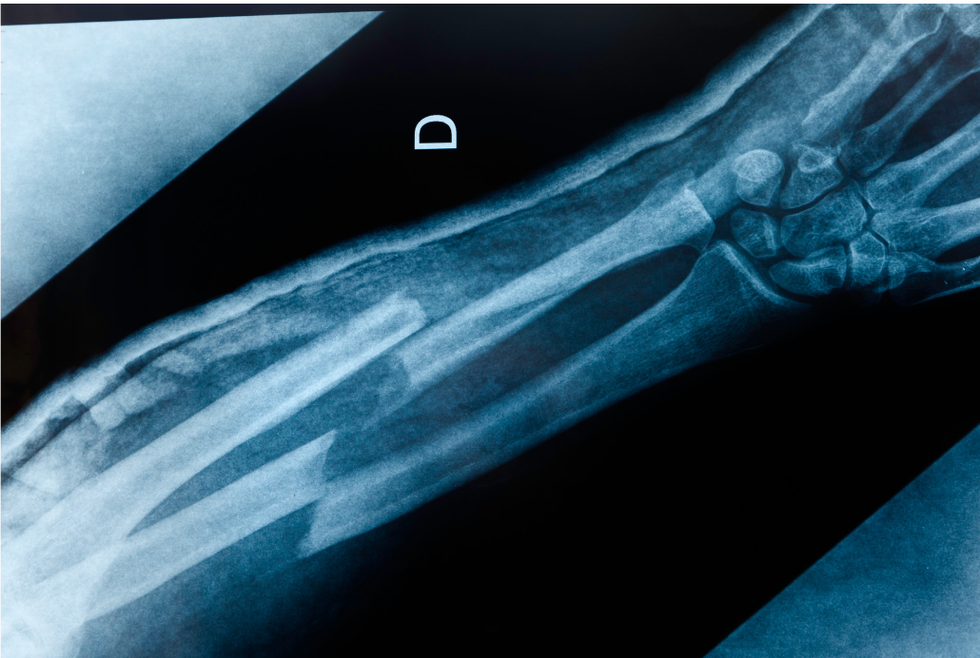

At the University of Oregon, scientists have created a potential medical breakthrough— well, technically a “mend-through.” These researchers have created tiny implants that could help speed up the healing process of mending broken bones.

That’s the issue the researchers at the University of Oregon tackled. They created a series of small implants with sensors that can provide data in real time at the injury site to help better determine if a bone needs more resistance rehab or if it has been overworked. In a technological study, the implants “significantly improved” the healing time for broken femurs in lab rats, cutting down a healing time from four-to-six months down to as little as eight weeks.

“One of the most impactful aspects of this work is that our resistance rehabilitation could regenerate the femur to normal strength within eight weeks without biological stimulants, and we’re really excited about that,” said study leader Dr. Kylie Williams.

While monitoring their bones using the sensors, the researchers found that the rodents that were given proper physical therapy in their exercise wheels with increasing resistance to promote building strength had their femurs heal much faster and more effectively than rodents that were sedentary. This included rodents that needed their training lowered at times depending on the data retrieved from the sensors.